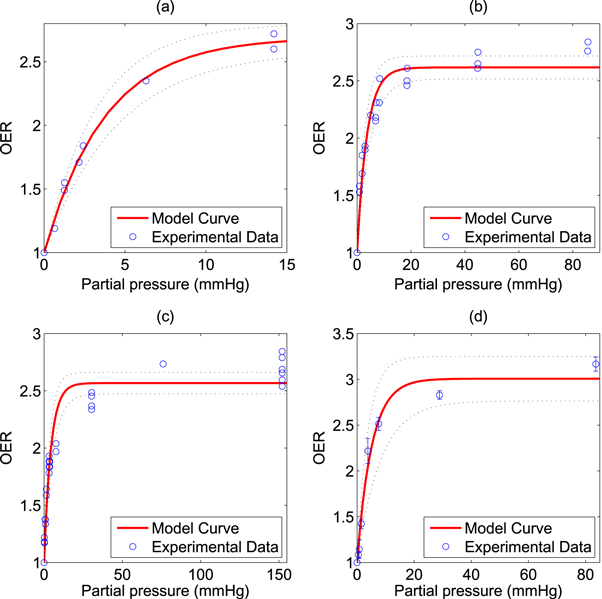

The model was fitted to the experimental data and goodness of fit calculated and 95% confidence intervals using a nonlinear least squares algorithm, illustrated in figure 2. All points were then pooled and the same analysis was performed, illustrated in figure 3. Results and estimated values are shown in table 4, yielding good fits to experimental data.

Figure 2. Model fit to historical OER data from (a) Koch et al (b) Whillians and Hunt (c) Ling et al (a) (d) Ling et al (b). 95% confidence intervals shown by dotted black lines.

Download figure:

Standard image High-resolution imageFigure 3. Model fit from combined data sets shown with (a) standard x-axis (b) logarithmic X-axis for clarity. 95% confidence intervals shown by dotted black lines.